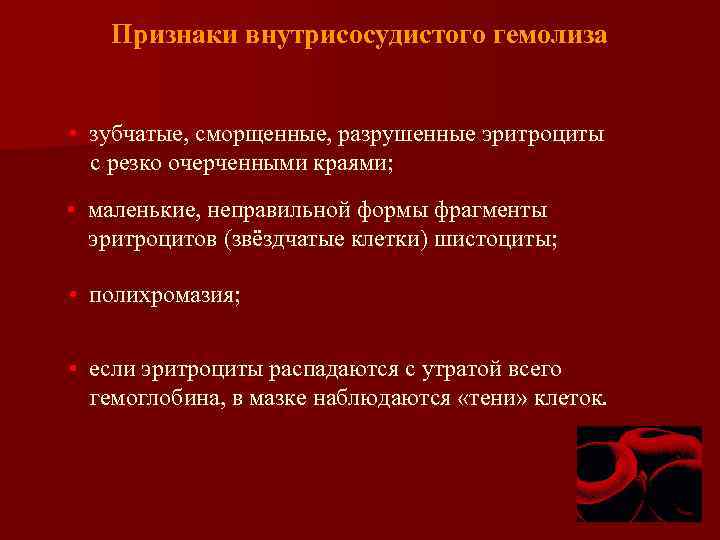

Признаки внутрисосудистого гемолиза • зубчатые, сморщенные, разрушенные эритроциты с резко очерченными краями; • маленькие, неправильной формы фрагменты эритроцитов (звёздчатые клетки) шистоциты; • полихромазия; • если эритроциты распадаются с утратой всего гемоглобина, в мазке наблюдаются «тени» клеток.

Признаки внутрисосудистого гемолиза • зубчатые, сморщенные, разрушенные эритроциты с резко очерченными краями; • маленькие, неправильной формы фрагменты эритроцитов (звёздчатые клетки) шистоциты; • полихромазия; • если эритроциты распадаются с утратой всего гемоглобина, в мазке наблюдаются «тени» клеток.